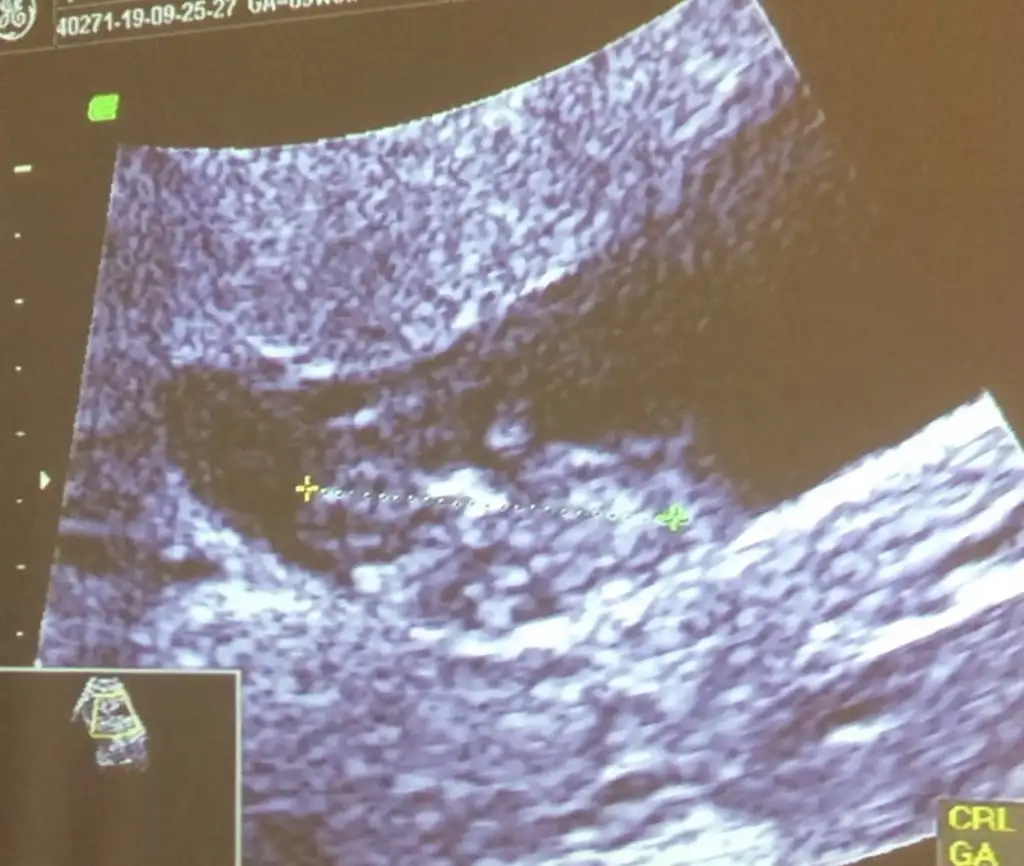

Başka usg varmı net degil erkek gibi geldi bana eminde olamadım12+2 ama yüzü donukmus tahmin varmi